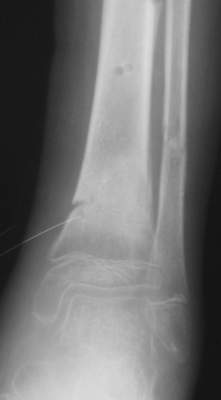

В январе 2005: варусная деформация н\3 голени, болевой с-м, комбинированная контрактура г\стопного сустава, нейропатия м\берцового нерва сохраняется слабость разгибания 1 пальца.

A> В январе 2005: варусная деформация н\3 голени,

А на вытяжении и в гипсповязке в течение 4 мес варуса видно не было?

Чего было ждать?

Есть даже тень периостальной костной мозоли и сросшийся перелом

малоберцовой кости.

Это сросшийся перелом малоберцовой кости. И ложный сустав

н\3 б\берцовой кости.

Вытяжение

|

Фиксация

в гипсе

Промежуточный